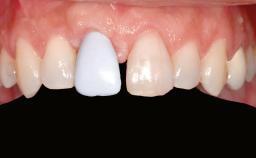

Guided Bone Regeneration (GBR) with a Particulated Autologous Graft and a ePTFE-Reinforced Membrane for Vertical Augmentation of a Single-Tooth Edentulous Space in the Esthetic Zone

A 47-year-old Caucasian woman with a single-tooth edentulous space at the site of the left maxillary canine was referred for treatment. She had undergone traumatic extraction of this impacted canine several months before referral. Her chief complaint was the dissatisfying appearance of her smile. The patient desired a stable and esthetic rehabilitation of the site. Her dental history showed no evidence of periodontal disease or bruxism. She had no systemic diseases, was not taking any medications, and did not smoke. The extraoral examination revealed a high lip line and an inadequate soft-tissue volume at the defective canine site. Large black triangles were visible between the canine and its adjacent teeth.

Prosthesis Type FDP

Defining Characteristics One missing tooth to be replaced by an implant-borne crown